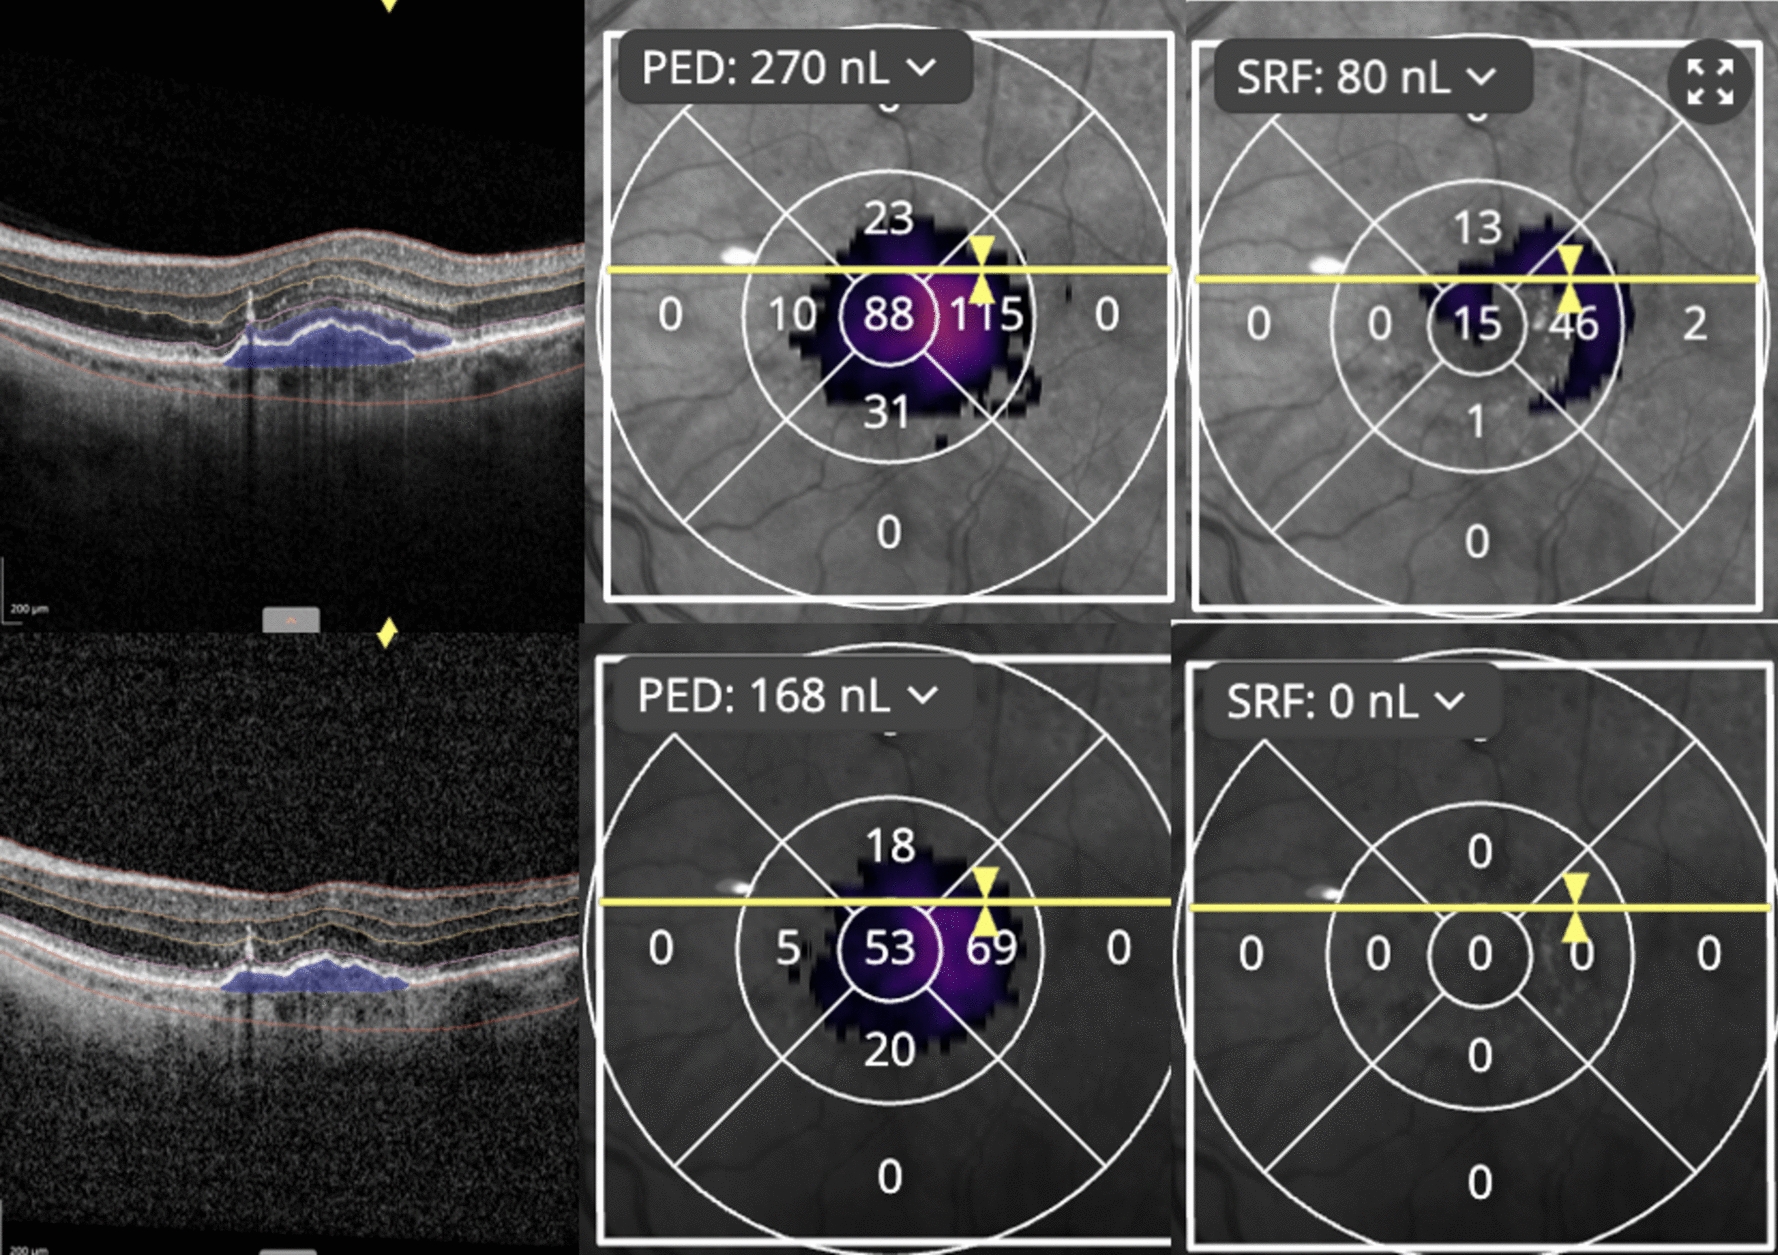

Methods: A retrospective case series study of 22 eyes with unresponsive CNV, despite monthly intravitreal treatment (mean number of pre-faricimab injections: 35.52 ± 17.12). We evaluated therapeutic response in eyes with persistent intra/subretinal fluid (IRF/SRF) unresponsive to anti-VEGF double-dose (DD) monotherapy (4-mg aflibercept) and/or simultaneous DD anti-VEGF (4-mg aflibercept) with steroids (triamcinolone). Best-corrected visual acuity (BCVA), intraocular pressure (IOP), and optical coherence tomography (OCT) measurements of central retinal thickness (CRT) were recorded for 7 follow-ups. Baseline and follow-up OCTs were examined by an AI-developed platform (Discovery OCT Fluid and Biomarker Detector, RetinAI AG, Switzerland) to measure the volume of IRF, SRF, and pigment epithelium detachment (PED) in nanoliters (nL) and CRT in micrometers (μm). Paired t-test compared these parameters at baseline and after treatment. OCTA analysis of CNV before and after treatment with faricimab was conducted using Angio-Tool software.

Results: Anatomic outcomes included mean CRT reduction of -25.3 μm (p = 0.0118) at month-1, -16.15 μm (p = 0.0414) at month-4, and -26.36 μm (p = 0.0129) after the 7th follow-up. AI-assisted software analysis showed a significant reduction of IRF, SRF, and PED volume at multiple time points after initiating faricimab. There was a non-significant improvement in BCVA.